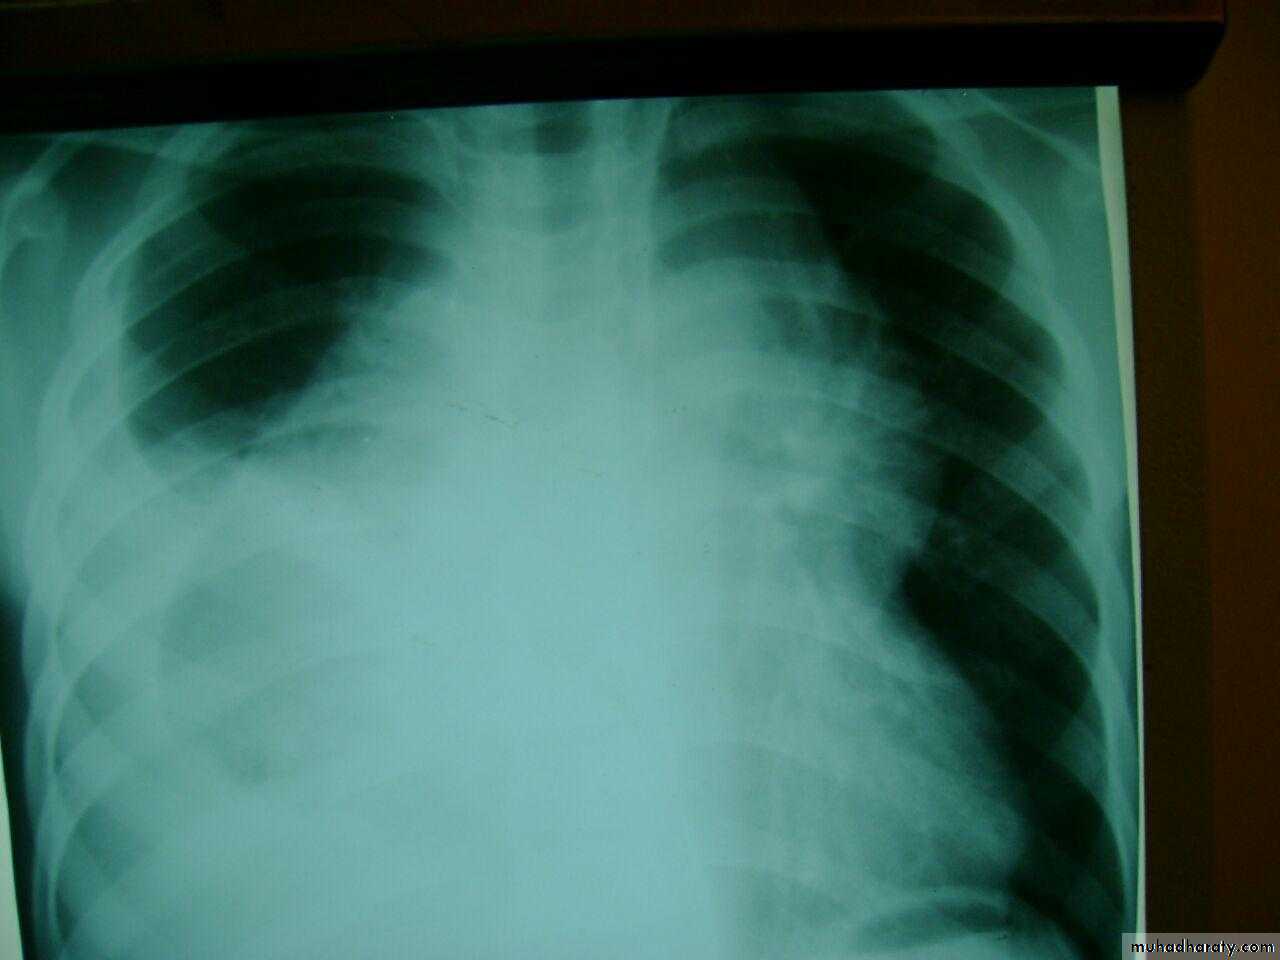

Homgenous opacity filling the rt. Hemithorax there is shefting in trachea to rt. Side mean this is collapse

Rt. Total lung collapse